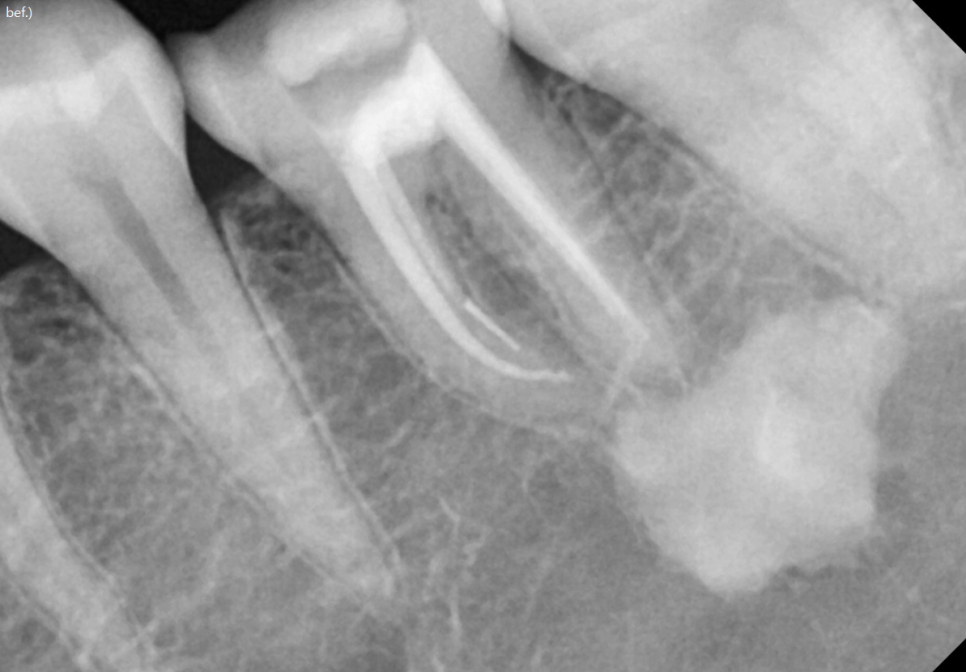

230531 임신 6개월에 신경치료를 받은 환자분